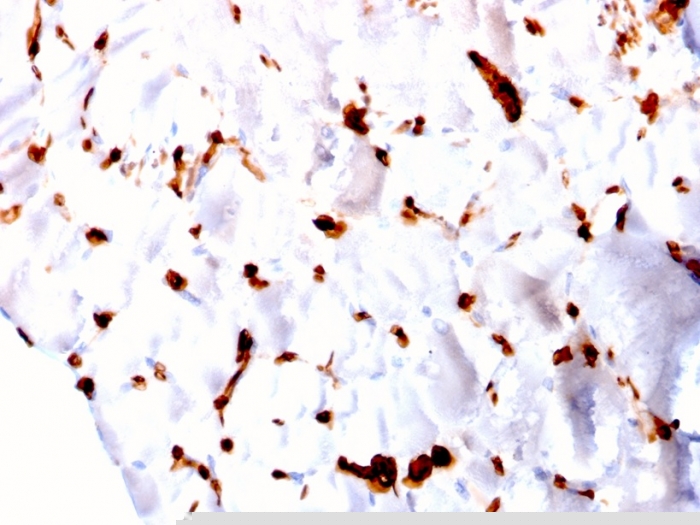

img

Formalin-fixed, paraffin-embedded human skeletal muscle stained with FABP5 Mouse Monoclonal Antibody (CPTC-FABP5-3).